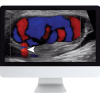

AIUM Fetal Echocardiography Guideline Tutorial

AIUM Fetal Echocardiography Guideline After viewing this tutorial, the learner will be able to describe the sonographic appearance of the fetal heart, and demonstrate ultrasound views for a comprehensive evaluation of the fetal heart in the second trimester of pregnancy. The learner attributes addressed are medical knowledge, patient care, and practice-based learning and improvement.